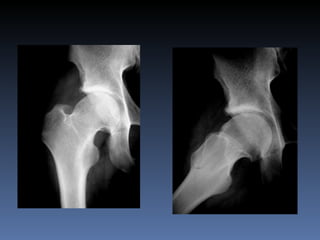

Un paciente de 25 años que trabaja como bodeguero ha experimentado dolor en su cadera derecha durante un año, empeorado por estar sentado o acostado. Su arco de movilidad articular está limitado, especialmente la rotación interna. Una artroresonancia y radiografías posteriores a la cirugía se realizaron para diagnosticar y tratar el problema.